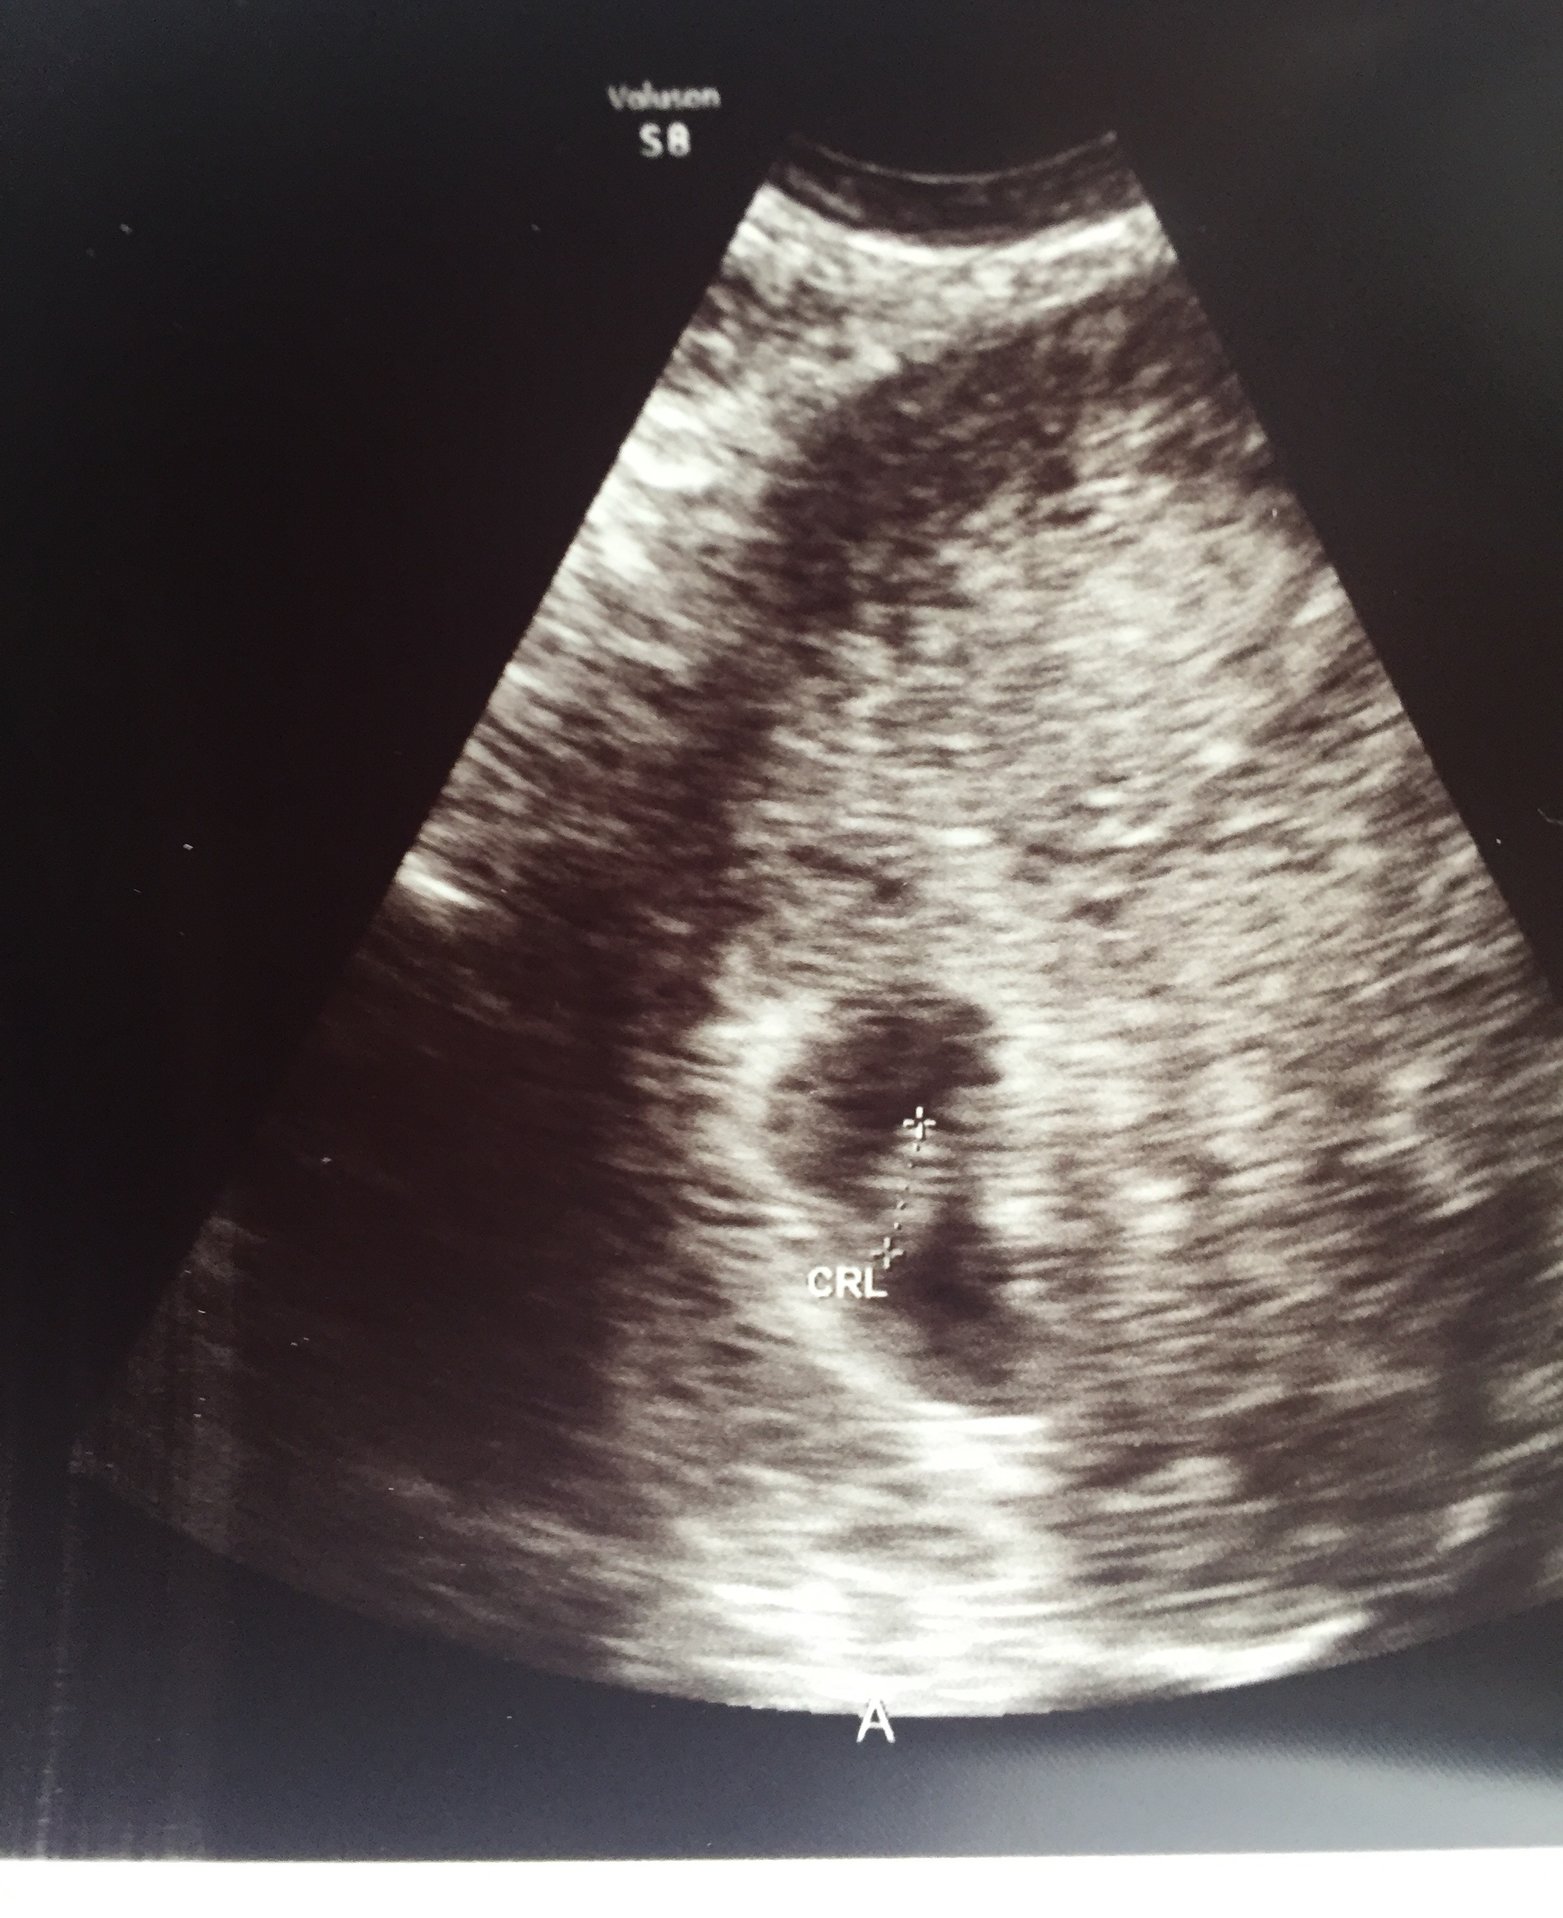

• @EmilyE13 thought your u/s was tomorrow but must be getting my dates wrong!  Congrats on your two little beans! They are beautiful and so happy you could hear the heartbeat.

• @EmilyE13 that's amazing!! Congrats! Thabks for sharing the beautifl pictures.

• @emilye13 your precious babies!!!!! I'm so glad to hear they are healthy little peanuts! <3

@EmilyE13. What beautiful sonogram pics so happy for you good luck on the healthy process of your pregnancy